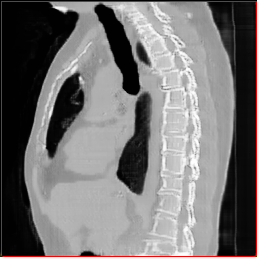

MAISI-v2 Controlnet qualitative Results:

Figure 5 shows qualitative results for MAISI-v2 Controlnet on 5 types of tumors.

Lung Tumor

0.75×0.75×0.60.75\times 0.75\times 0.6

mm

512×512×512512\times 512\times 512

Liver Tumor

0.75×0.75×0.50.75\times 0.75\times 0.5

512×512×768512\times 512\times 768

Panc. Tumor

1×1×11\times 1\times 1

Colon Tumor

0.75×0.75×1.50.75\times 0.75\times 1.5

512×512×256512\times 512\times 256

Bone-Les

1×1×1.31\times 1\times 1.3

512×512×384512\times 512\times 384

Figure 5: MAISI-v2 segmentation-guided results for five types of tumors. We show results for different voxel spacing and volume size to demonstrate the flexibility of MAISI-v2. Different Hounsfield Unit window is used to better show the contrast between tumor and normal tissues.